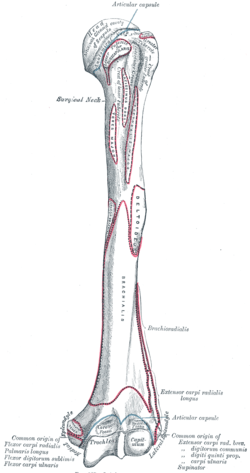

Upper extremity of humerus

Left humerus. Anterior and posterior views. | |

The upper or proximal extremity of the humerus consists of the bone's large rounded head joined to the body by a constricted portion called the neck, and two eminences, the greater and lesser tubercles.

Tubercles

The greater tubercle (tuberculum majus; greater tuberosity) is situated lateral to the head and lesser tubercle, and just lateral to the anatomical neck. Its upper surface is rounded and marked by three flat impressions: the highest of these gives insertion to the supraspinatus muscle; the middle to the infraspinatus muscle; the lowest one, and the body of the bone for about 2.5 cm. below it, to the teres minor muscle. The lateral surface of the greater tubercle is convex, rough, and continuous with the lateral surface of the body.[1]

The lesser tuberosity or lesser tubercle (tuberculum minus; lesser tuberosity), although smaller, is more prominent than the greater: it is situated in front, and is directed medialward and forward. Above and in front it presents an impression for the insertion of the tendon of the subscapularis muscle.[1]

Bicipital groove

The tubercles are separated from each other by a deep groove, the bicipital groove (intertubercular groove), which lodges the long tendon of the biceps brachii muscle and transmits a branch of the anterior humeral circumflex artery to the shoulder-joint. It runs obliquely downward, and ends near the junction of the upper with the middle third of the bone. In the fresh state its upper part is covered with a thin layer of cartilage, lined by a prolongation of the synovial membrane of the shoulder-joint; its lower portion gives insertion to the tendon of the latissimus dorsi muscle. It is deep and narrow above, and becomes shallow and a little broader as it descends. Its lips are called, respectively, the crests of the greater and lesser tubercles (bicipital ridges), and form the upper parts of the anterior and medial borders of the body of the bone.[1]